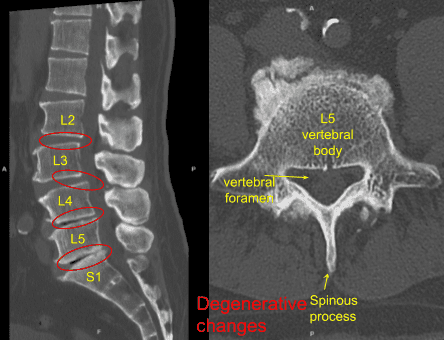

Me hicieron una resonancia magnética que mostró cambios degenerativos de L2 a S1 con retrolistesis en L2-L3, anterolistesis de grado 1 en L3-L4, fenómenos de vacío en L4-5 y L5-S1 con pérdida de espacio discal en L4-L5 y L5-S1.